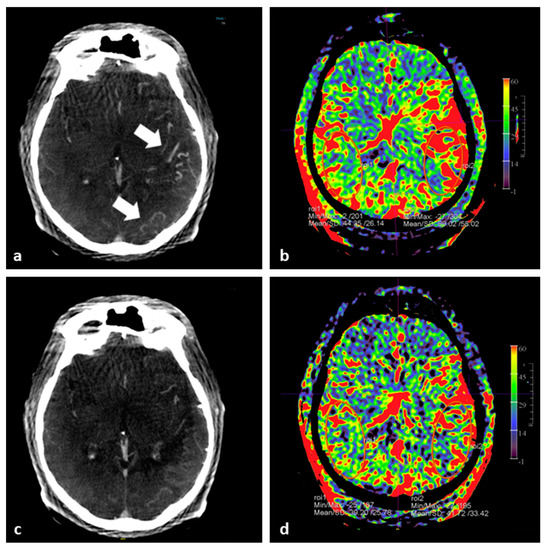

- O’Connor, K.P.; Milton, C.K.; Strickland, A.; Apple, B.; Bohnstedt, B.N. Flat-Detector CT to Quantify Response to Intra-Arterial Spasmolytic Therapy for Cerebral Vasospasm. J. Neuroimaging 2020, 30, 227–232. [Google Scholar] [CrossRef]